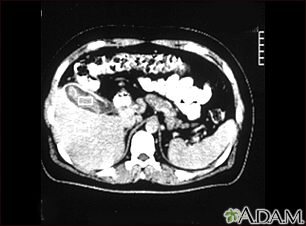

Cholecystitis, CT scanBackCholecystitis, CT scanThis is a CT scan of the upper abdomen showing cholecystitis (gall stones). E-mail FormEmail ResultsName:Email address:Recipients Name:Recipients address:Message: